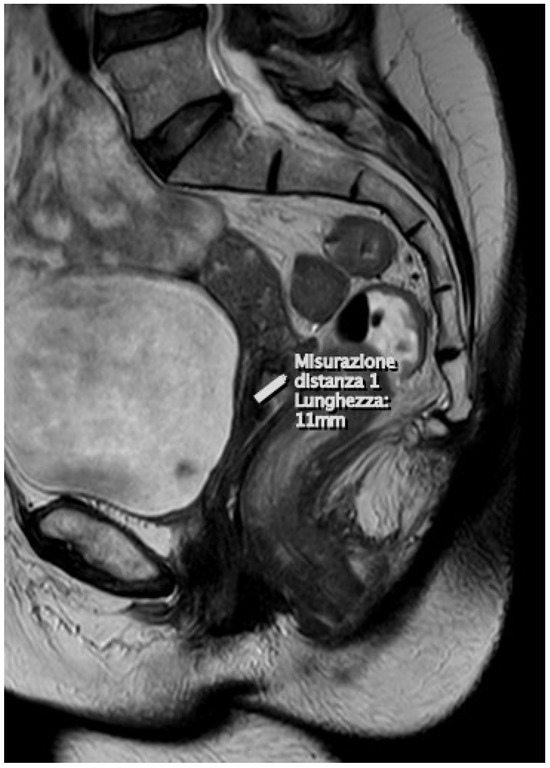

3. Results

4. Magnetic Resonance Imaging and Treatment of Early Cervical Cancer

4.1. Magnetic Resonance Imaging: Protocol

4.2. T2-Weighted Images (T2WI)

4.3. Diffusion-Weighted Images (DWI)